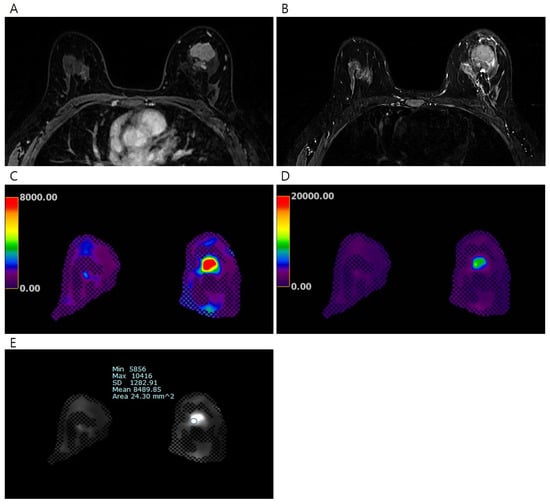

| Normal Fat Tissue | Normal Fibroglandular Tissue | Cancer | p-Value a | p-Value b | |

|---|---|---|---|---|---|

| Mean elasticity value (kPa) | 1.32 ± 0.33 | 2.54 ± 0.80 | 7.90 ± 5.80 | <0.001 | <0.001 |

| Maximum elasticity value (kPa) | 1.37 ± 0.34 | 2.70 ± 0.86 | 11.79 ± 11.52 | <0.001 | <0.001 |

| Minimum elasticity value (kPa) | 1.26 ± 0.33 | 2.35 ± 0.73 | 5.28 ± 3.87 | <0.001 | <0.001 |